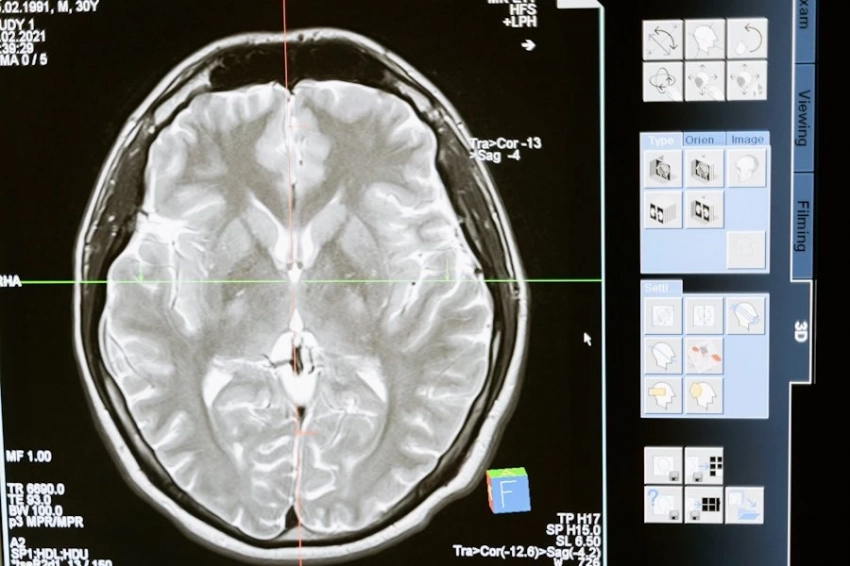

Исследователи планируют продолжить исследования этого препарата для лечения других видов рака, например, для глиобластомы (рак мозга).